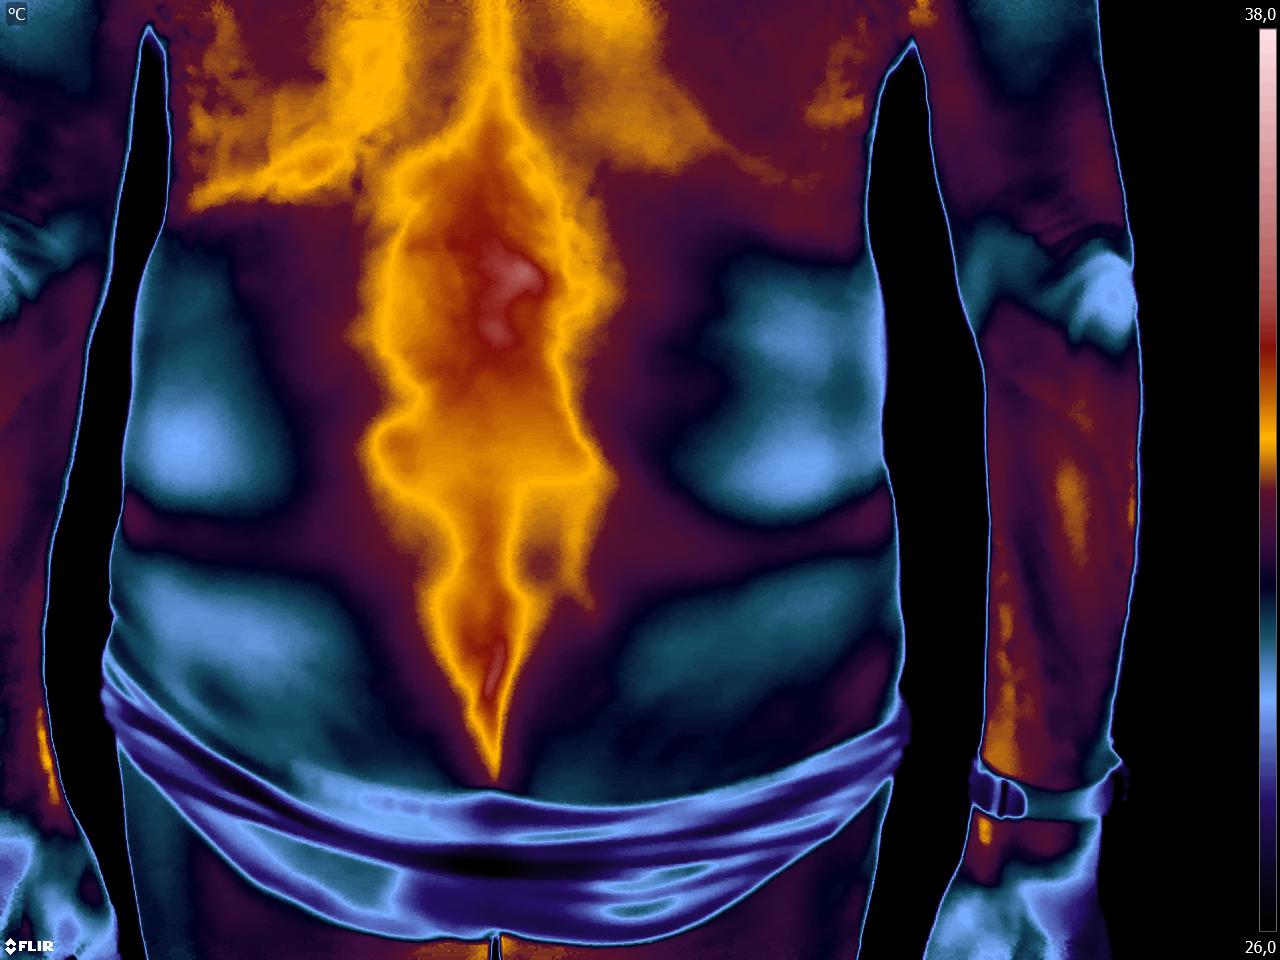

Caros colegas fisioterapeutas e terapeutas ocupacionais, vocês sabiam que com a Termofuncional pode-se detectar disfunções decorrentes da atividade física realizada […]

Colegas fisioterapeutas e terapeutas ocupacionais, vocês sabiam que com o estudo da Termofuncional é possível detectar a disfunção do se […]